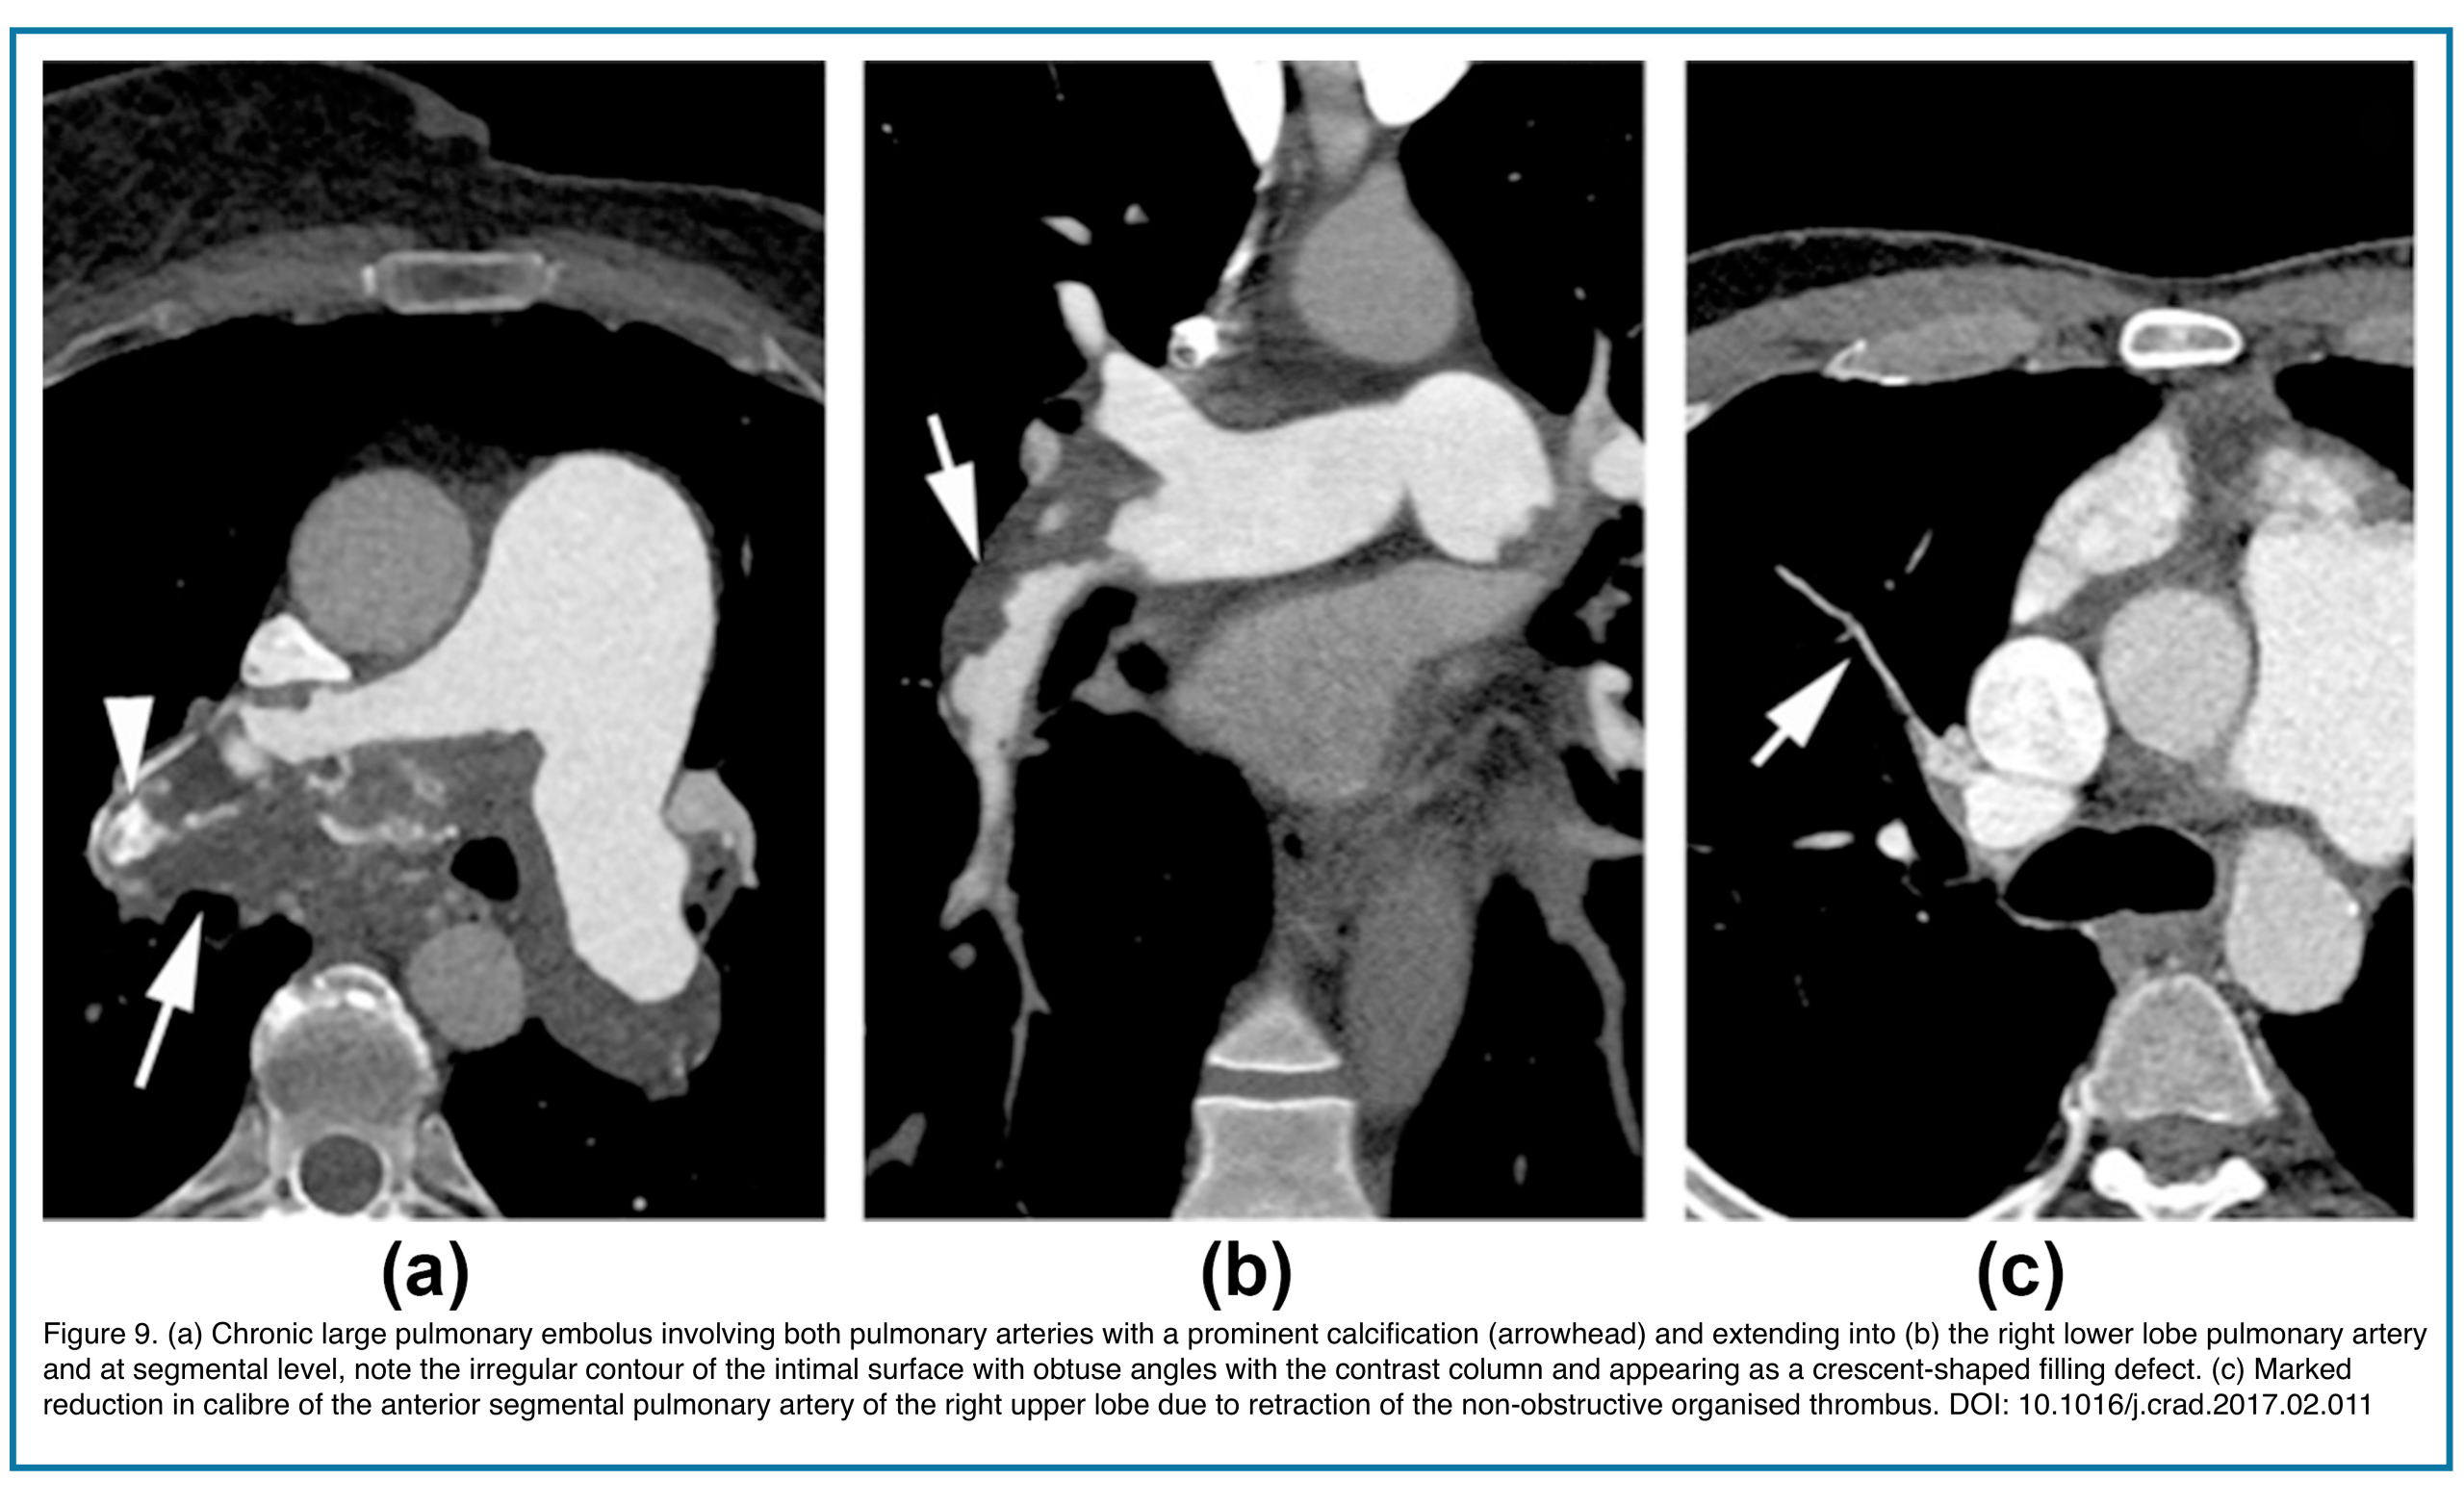

B. Pulmonary Artery Remodeling

- Vessel shrinkage

- Complete occlusion of a pulmonary artery branch that is permanently smaller than other arteries of the same order (an important distinguishing feature from acute PE, where vessels are often normal or enlarged). Figure 8.

- Vessel Stenosis or Irregularity: Long segments of narrowing or “bizarre, corkscrew” tortuosity of distal arteries due to recanalization.

- Calcification within the chronic clot (rare, but pathognomonic). Figure 9.